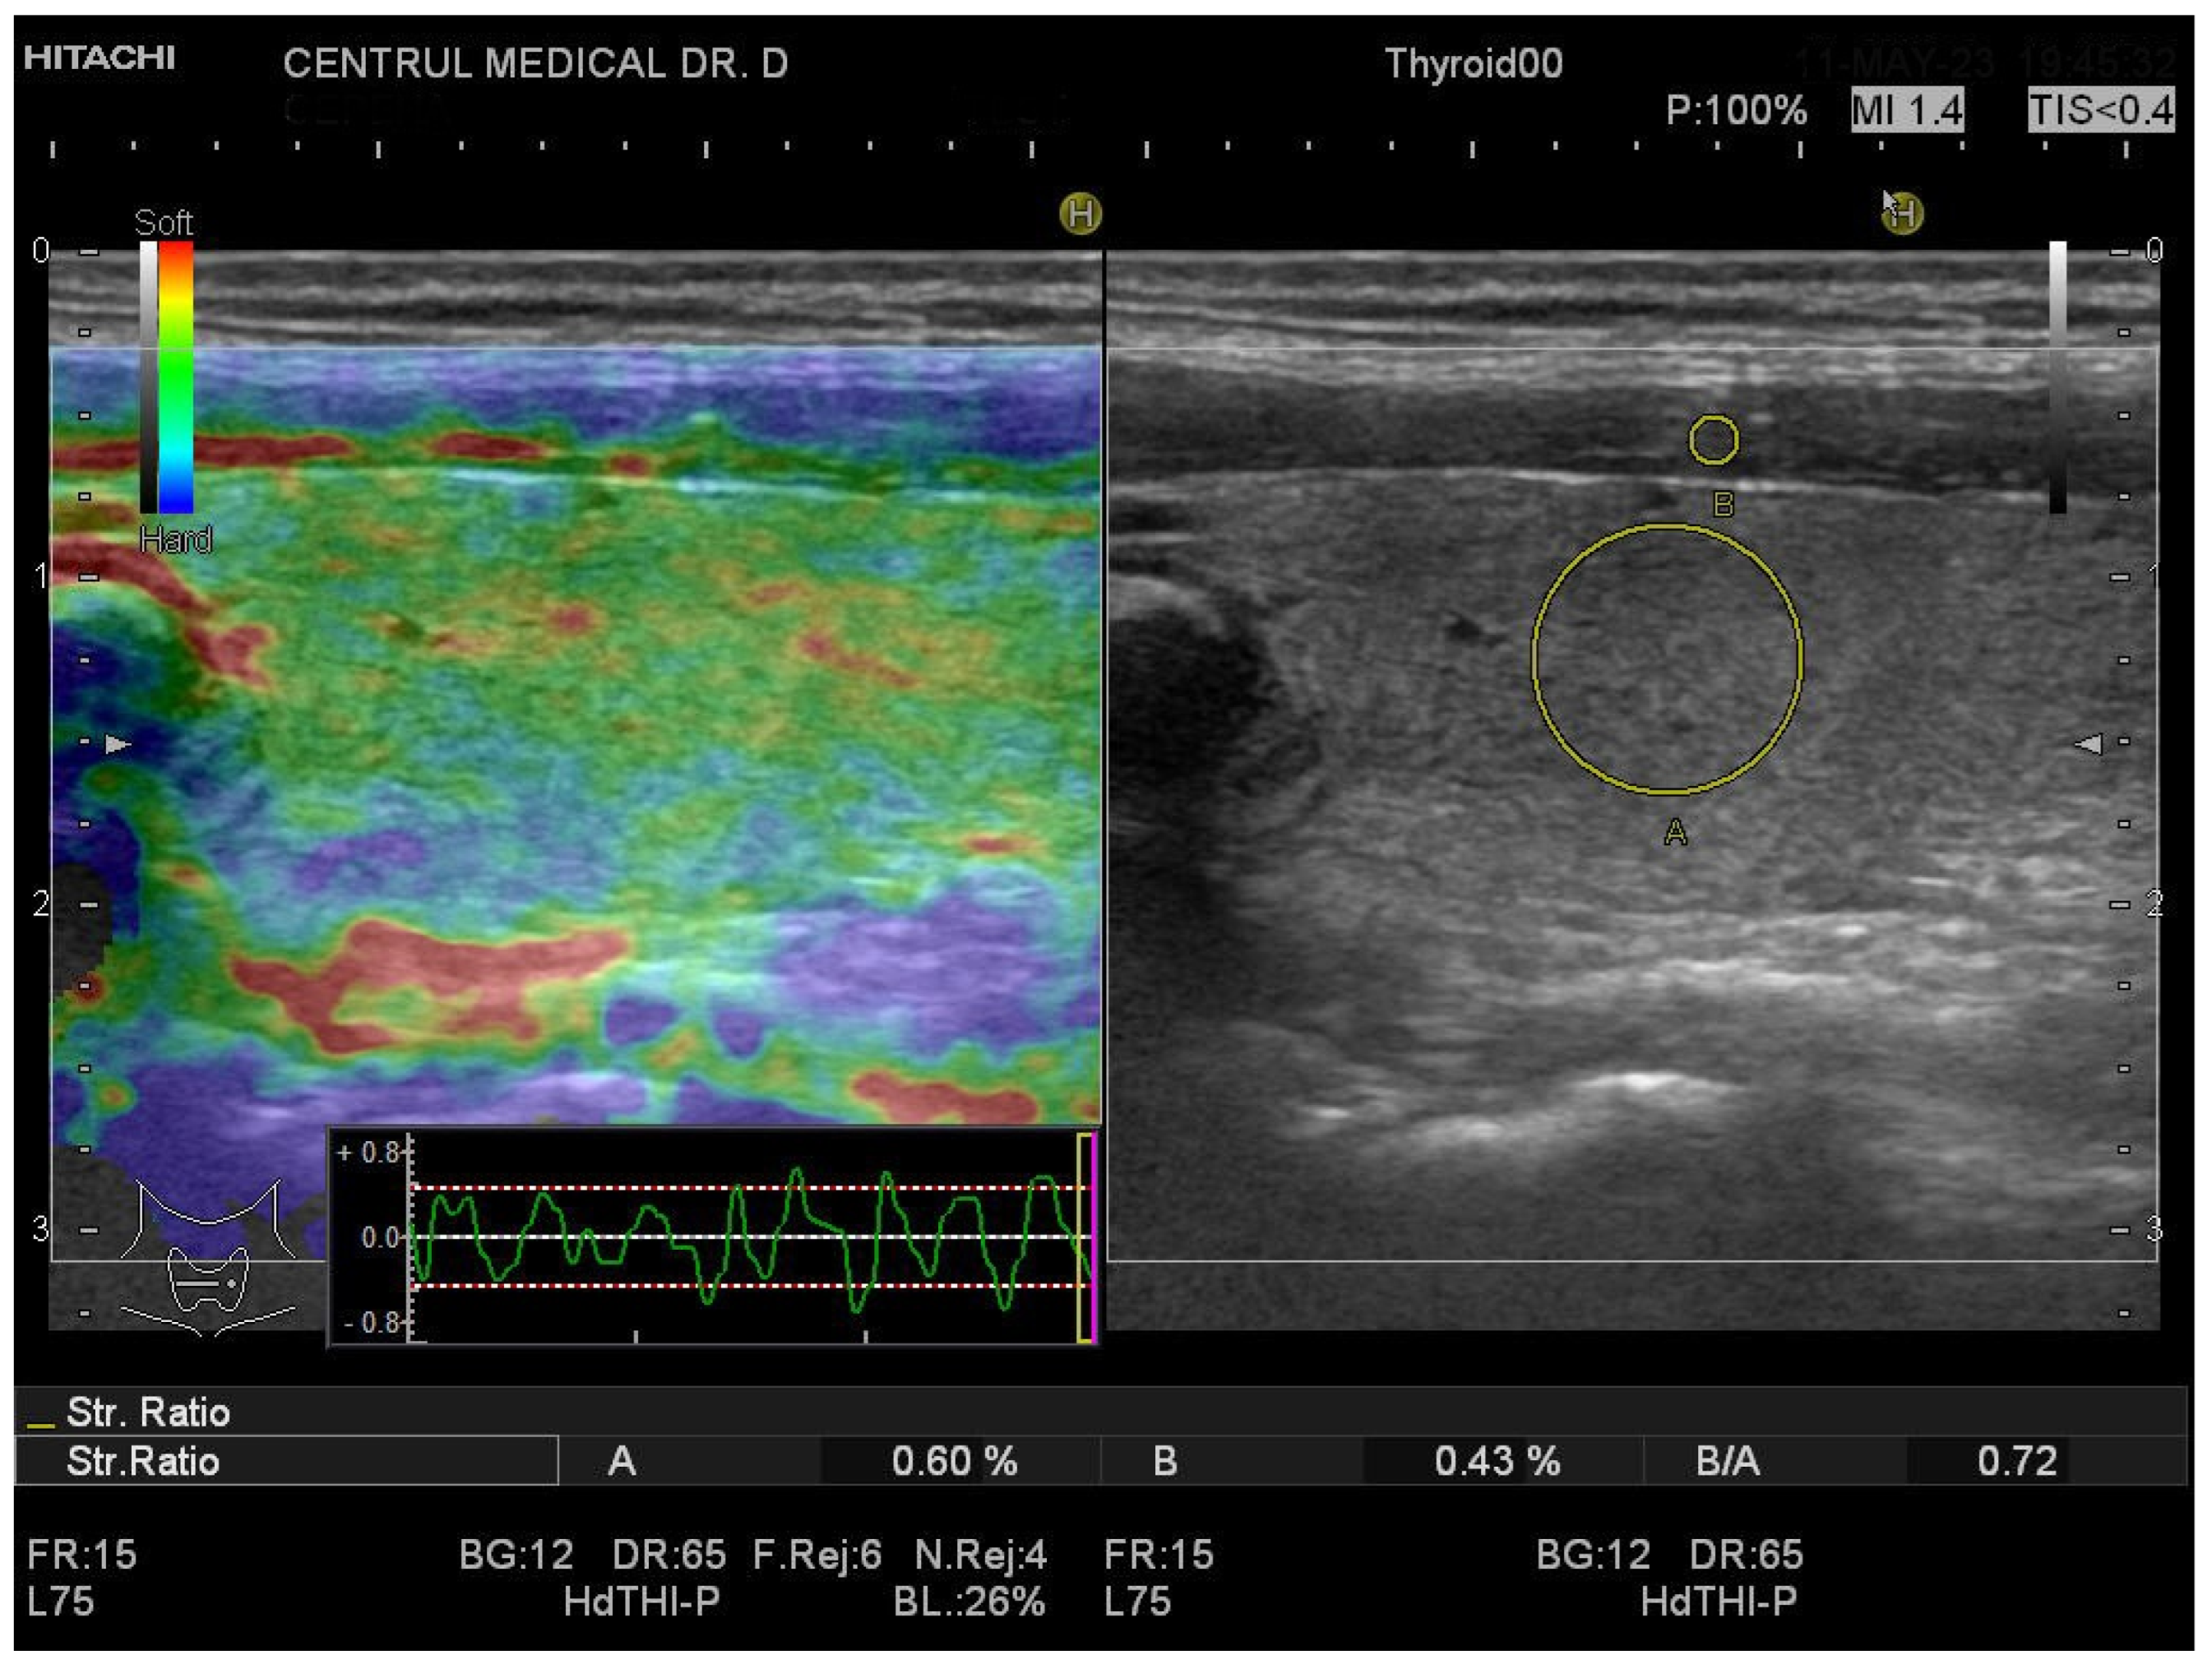

2.4. Conventional Ultrasound and Elastography Examination

3.1. Strain Elastography Measurements